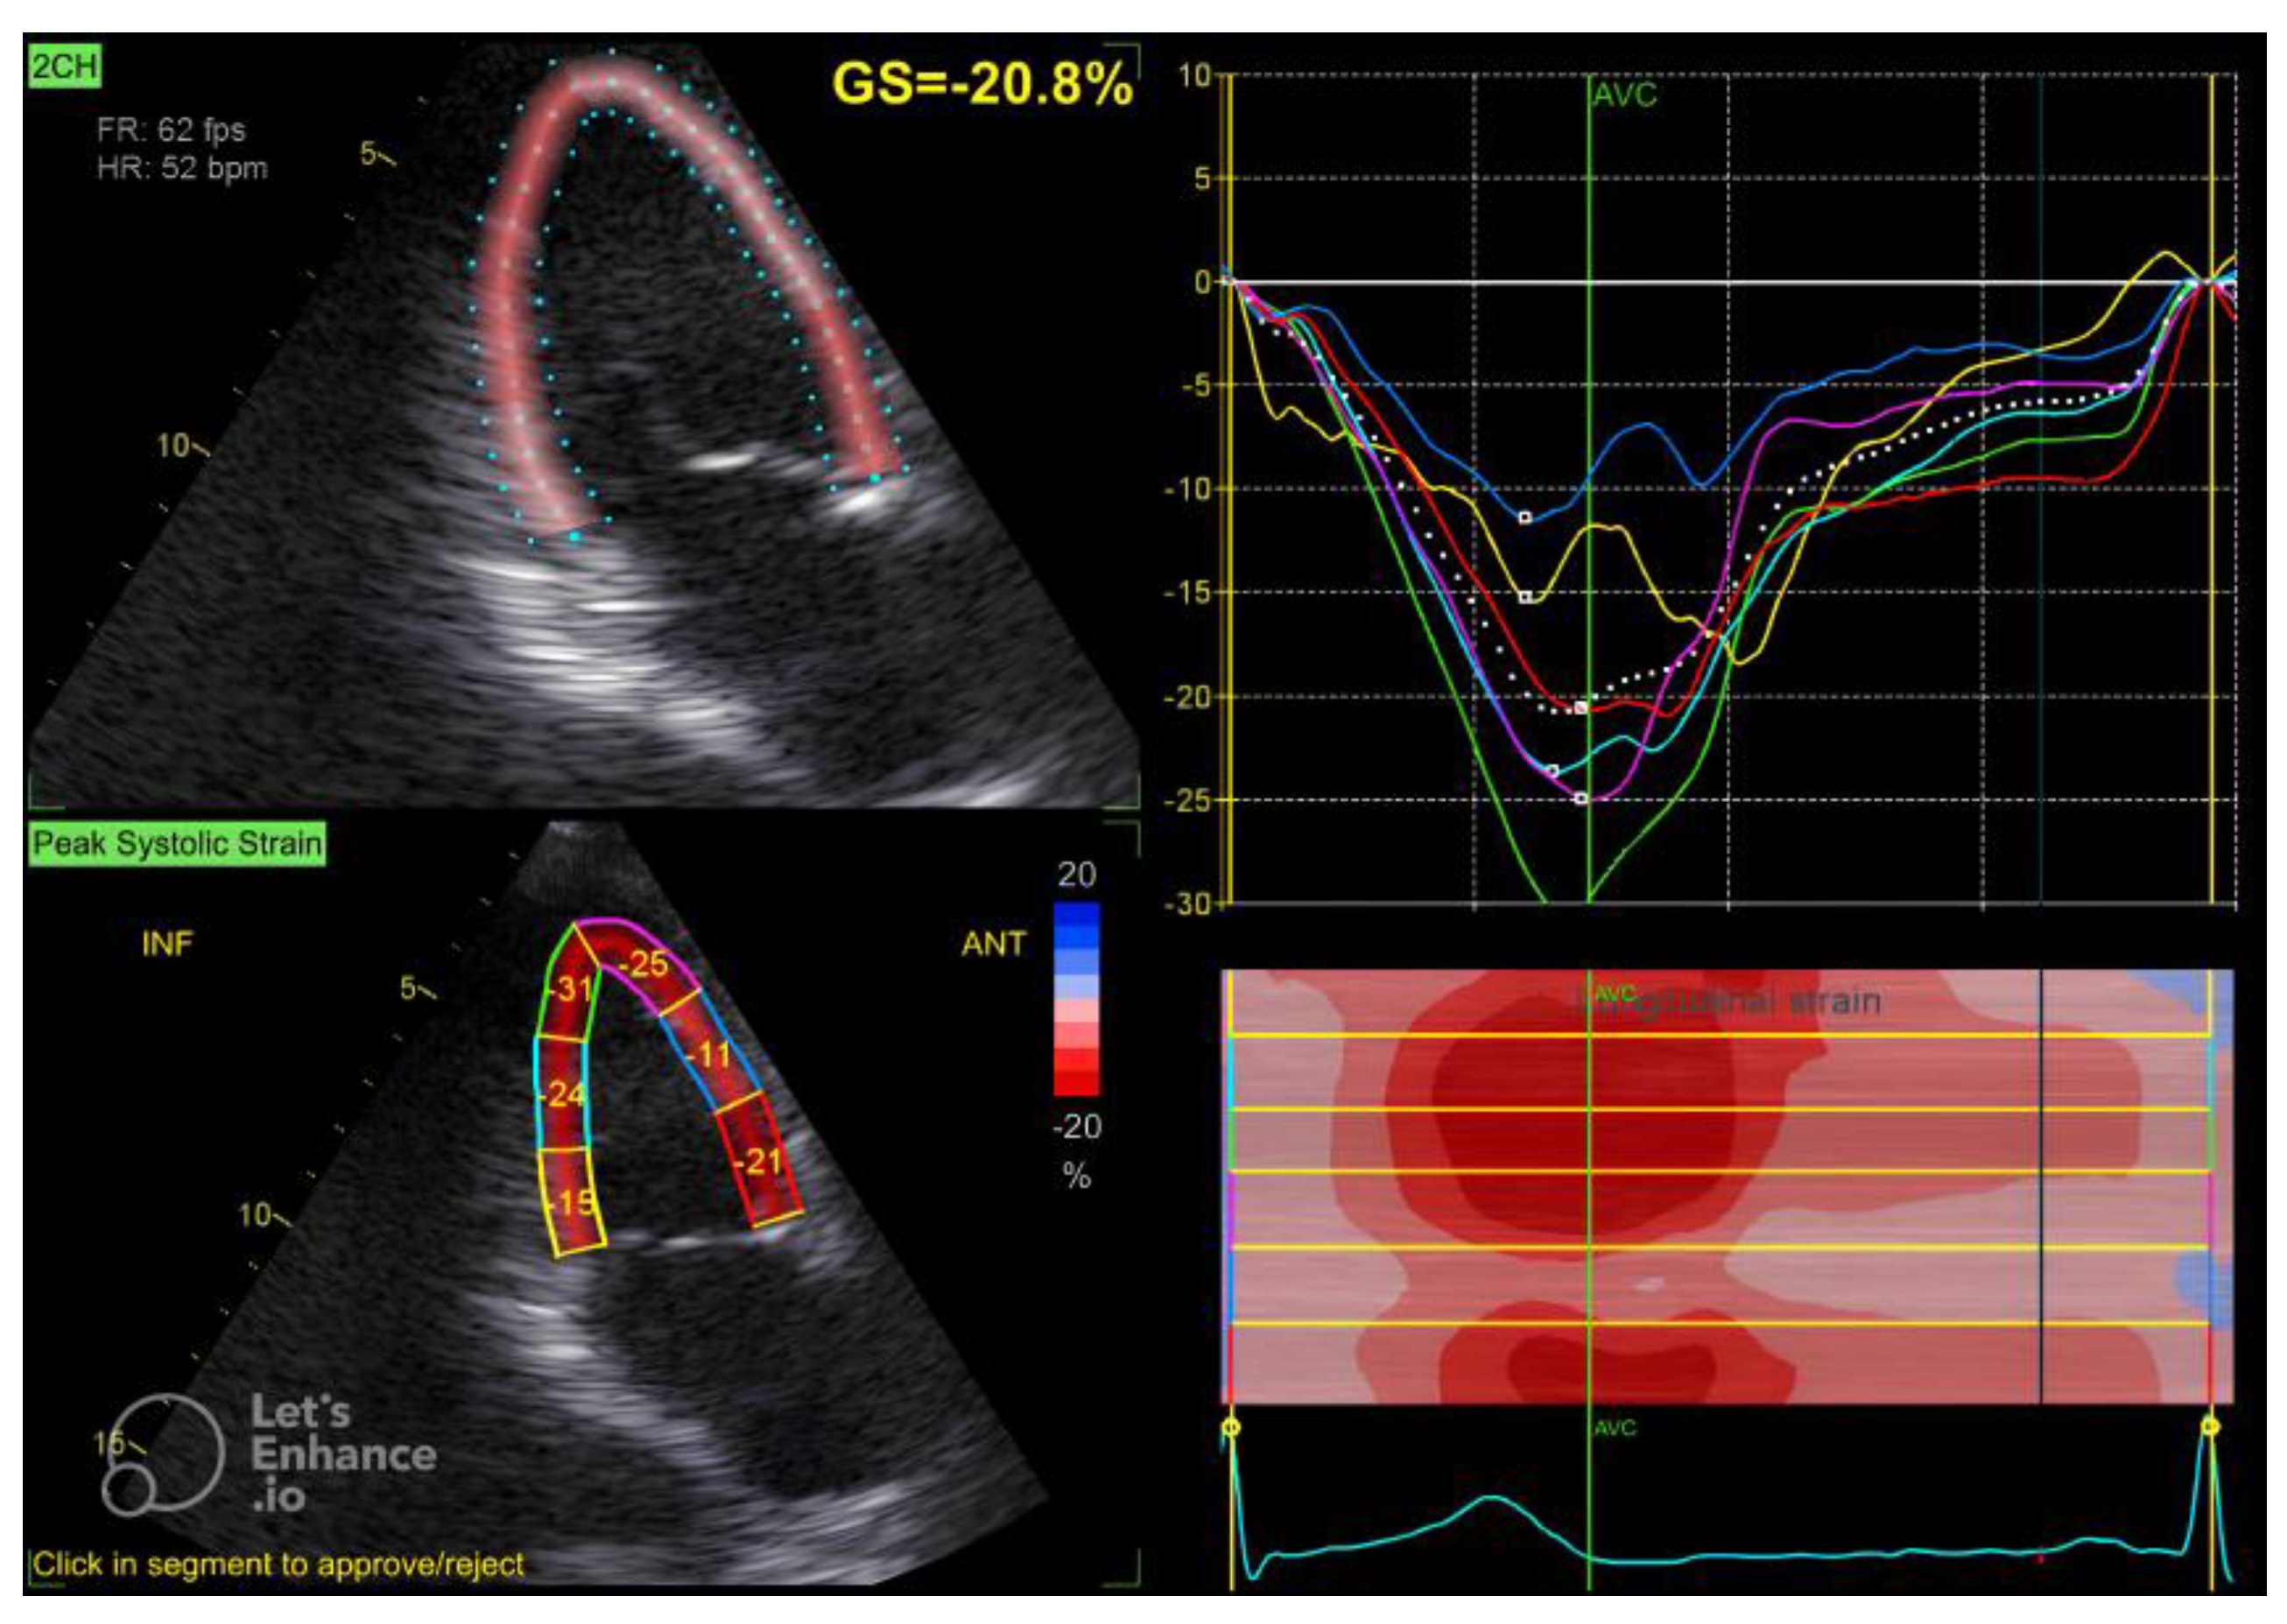

2.2. Echocardiographic Assessment

| GLS (%) | −20.25 ± 2.53 |